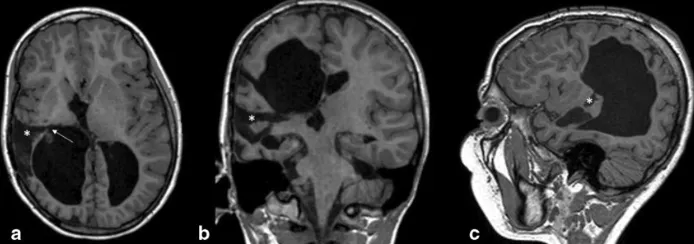

图3:术后MRI随访显示右侧岛周功能断联手术区域的结构变化,图中标注了岛周夹层的范围以及上颞回、中颞回切除后的影像改变,箭头指示内囊离断延伸至侧脑室房部。

图5:患者感觉运动结构损伤与功能重组的多模态MRI综合评估。轴位T1-MPRAGE图像显示右侧脑室周围白质软化病变,病变广泛累及中央前回与中央后回,并延伸至丘脑后部及内囊后肢。在DTI微观结构分析中,右侧皮质脊髓束纤维与健侧相比显示不清;纤维束追踪重建亦显示右侧纤维束数量和走行长度明显少于左侧,两侧存在显著不对称。功能评估结果叠加于解剖MPRAGE图像之上显示:右手被动运动及感觉任务均在左侧中央前回与中央后回引发了明确激活;左手被动运动任务在同侧左侧中央前回水平亦触发了激活,但感觉任务未见显著激活;所有任务条件下,右侧大脑半球均未检测到显著激活,图像以放射学惯例方向呈现。